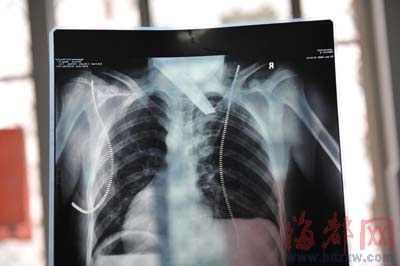

前晚,在第一醫(yī)院急救室,經(jīng)過4個多小時的搶救,醫(yī)生將匕首從小勇身上取出,發(fā)現(xiàn)這把匕首的刀尖扎斷了1厘米。由于小勇肺部被刺中,昨天上午,醫(yī)生再次進行了3個多小時的手術(shù),切除了受傷的部分肺,直到下午,小勇才挺過來!巴α艘灰梗F(xiàn)在總算醒了過來!睏钆恳灰箾]睡,守在手術(shù)室外7個多小時,生怕兒子再醒不過來。不過,由于傷勢嚴重,小勇目前戴著氧氣呼吸,仍未脫險。